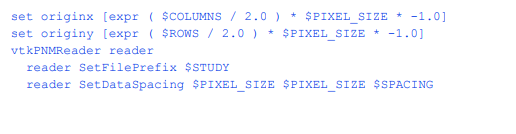

我们首先开发Tcl脚本来处理卷数据。在这些脚本中,我们使用用户指定的变量用大写字母表示的约定。首先,我们展示了管道的元素,随后展示了样本文件,提取青蛙组织的3D模型。

读取分段卷数据

我们在这里假设所有要处理的数据都是通过一个恒定的中心地标获得的。在VTK中,数据的原点应用于图像卷的左下角。在这个管道中,我们计算的原点是体积的x,y中心为(0,0)。dataspace描述了每个像素的大小和片之间的距离。DataVOI选择感兴趣的卷(VOI)。VOI可以让我们选择感兴趣的区域,有时可以消除无关的结构,如CT台床。对于青蛙,我们编写了一个小的C程序来读取组织标签文件,并为每个组织找到感兴趣的体积。

SetTransform()方法定义了如何在内存中排列数据。医学图像可以以不同的顺序获得。例如,在CT中,数据可以从上到下(上级到下级)收集,也可以从下到上(下级到上级)收集。此外,MRI数据可以从左到右、从右到左、从前到后(前到后)或从后到前获取。这个过滤器转换三角形顶点,这样得到的模型都将“面向”观看者,视角向上(0,-1,0),向下看正z轴。同时,保持适当的左右对应关系。这意味着病人的左侧将始终留在生成的模型上。查看SliceOrder。TCL来查看每个顺序的排列和旋转。

所有其他参数都是不言自明的,除了最后一个。在这个脚本中,我们知道管道将只执行一次。为了节省内存,我们调用ReleaseDataFlagOn()方法。这允许VTK管道在过滤器处理完数据后释放数据。对于大型医疗数据集,这可能意味着是否能够处理数据集之间的差异。